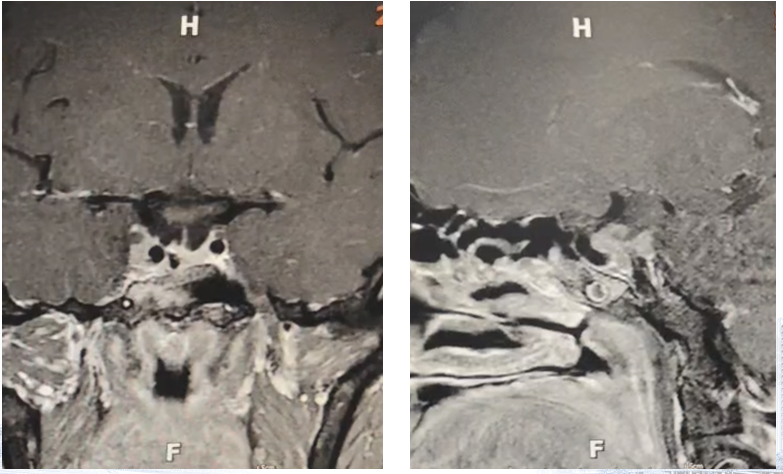

患者2021年5月于我院神外住院,术前GH >34.8 ng/ml,余激素正常;行开颅鞍区占位性病变切除+脑脊液漏修补术+颅神经微血管减压术,术后MRI:2.7×2.3×3.3cm。术后病理诊断为垂体腺瘤,免疫组化示P53(2+)、Ki-67(+,1%)。2021年9月复查提示肿瘤残余,2021年9-10月行术后放疗,放疗后强化灶较前稍缩小(1.5×1.9×1.6cm,增强中等强化)。

2021年11月评估激素提示GH >34.8 ng/ml,IGF-1 773.6 ng/ml,奥曲肽-生长激素抑制试验提示GH被抑制,遂完成24次奥曲肽微球30mg治疗(q4w;2021.11-2025.6),末次出院无不适,手部及额部紧绷感较前明显缓解,双手指间关节及双足趾间关节肥大较前明显缓解,可正常握拳。患者在整个治疗过程中未能规律接受奥曲肽治疗,但仍可见其对药物具有良好的生化应答,奥曲肽在该患者身上呈现出明确的疾病控制效果。需要指出的是,患者生化指标的周期性波动与其给药间隔不规律密切相关。

病例小结

本例患者因外伤检查偶然发现鞍区占位,进一步评估提示垂体瘤及瘤内出血。随后于2021年5月行开颅垂体瘤切除术,术后病理提示垂体腺瘤,Ki-67约1%,P53(2+)。尽管接受了术后放疗,但影像学仍提示明显肿瘤残余。术后激素水平持续升高,GH>34.8 ng/mL、IGF-1显著升高,提示生化缓解未达标。自2021年11月起分次给予奥曲肽微球治疗,共完成24次。临床上患者肢端肥大相关症状逐渐改善,包括额面部紧绷感减轻、手足关节肥大缓解,功能活动恢复良好。需要强调的是,患者在治疗期间未能规律接受奥曲肽治疗,给药间隔多次延长。然而,即便在不规律治疗的情况下,仍然能够观察到其激素水平的良好反应性,提示患者对奥曲肽高度敏感。规律使用生长抑素类似物对于维持生化控制具有重要意义。